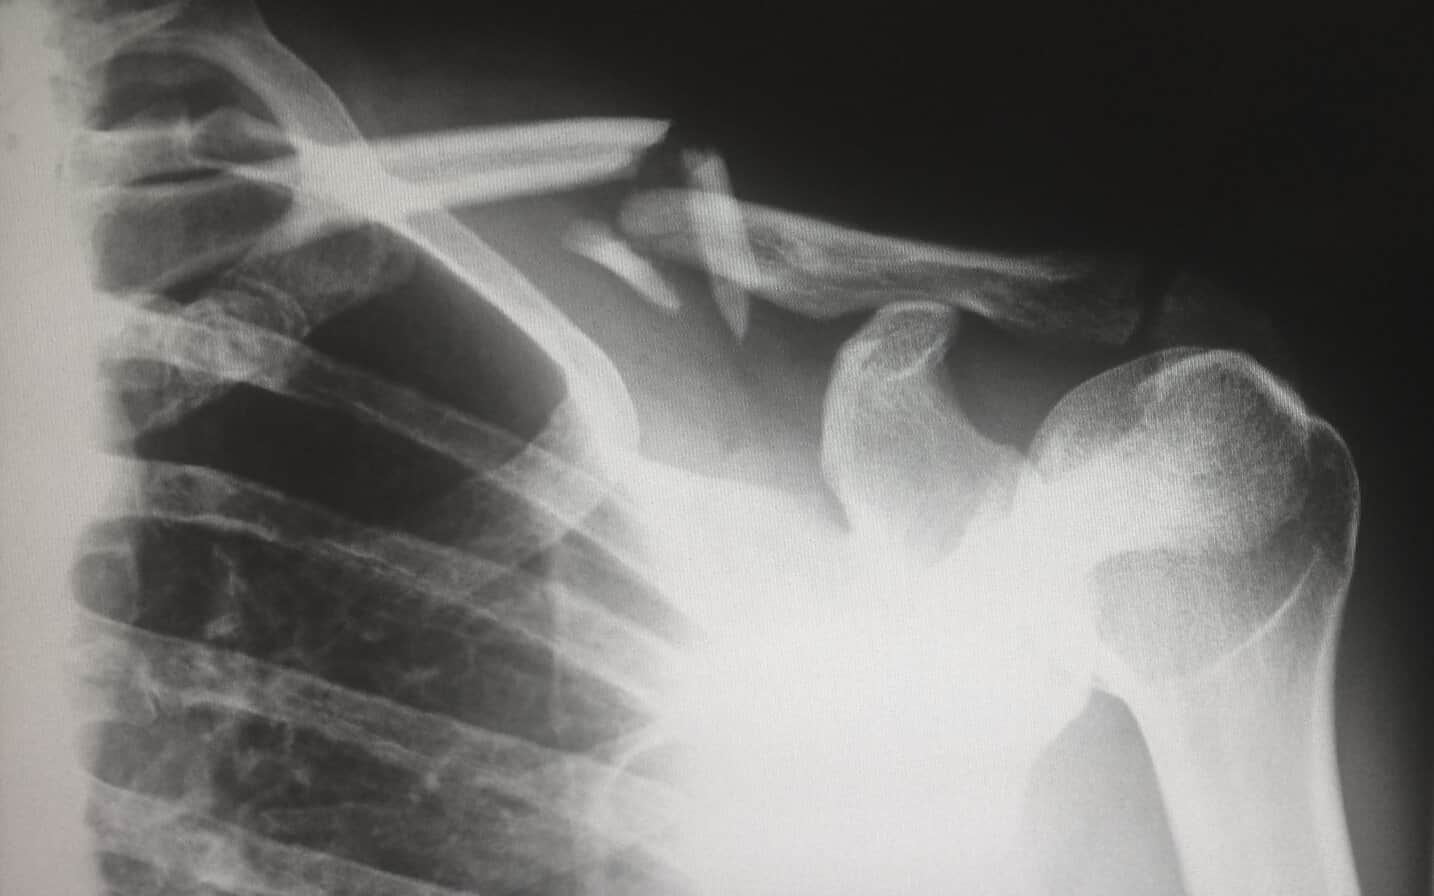

Сравнявайки активността на елементите: стронций, калций и силиций, можем да преценим, каква е вероятността да загубят здравето си днешните фенове на млякото. Стронцият е най-активният елемент от горе изброените. Ролята на неговото присъствие в човешкия организъм може да се види при заболяванията в областта Уров. При жителите на задбайкалската долина Уров в продължение на дълго време се появявали заболявания, проявяващи се с деформации и чупливост на костите. Тамошните животни също боледували. Оказало се, че във връзка с експлоатацията на залежи в горната част на река Уров, нейните води имат увеличено съдържание на стронций. При недостиг на силиций в организма, калцият е слабо усвоим и стронцият започва да го замества в костните тъкани. Стронция, обаче, не се задържа в организма за дълго време. След извършване на унищожителното си дело в човешките кости, се връща отново в природата, напуска тялото.